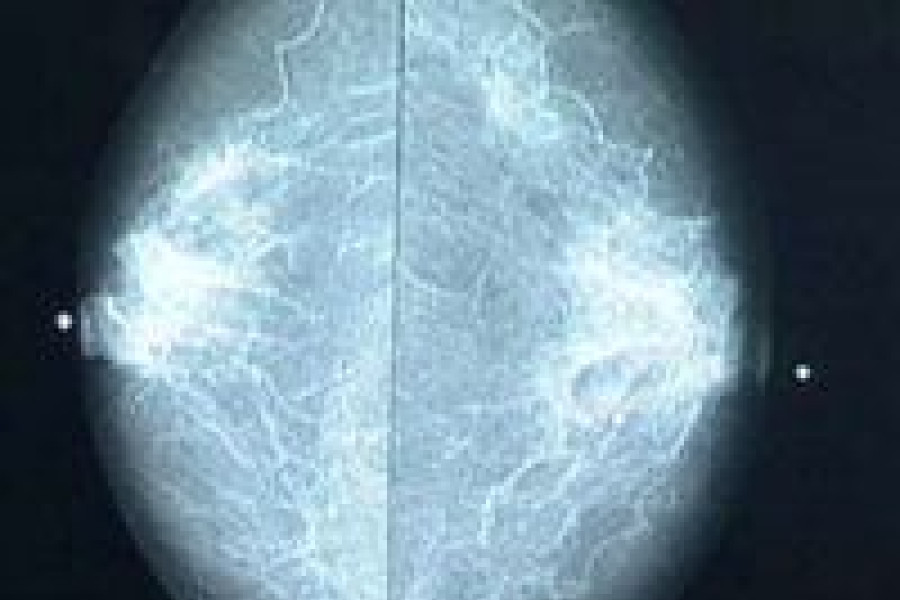

Mammografia, czyli rentgenowskie badanie piersi, to skuteczna metoda w diagnostyce wczesnych objawów raka piersi. Wczesne wykrycie tego nowotworu gwarantuje niemal 100% pewności na wyleczenie choroby, dlatego warto się badać. Co więcej, mammografia jest badaniem bezpiecznym i wykonywanym przy użyciu minimalnej dawki promieniowania rentgenowskiego.